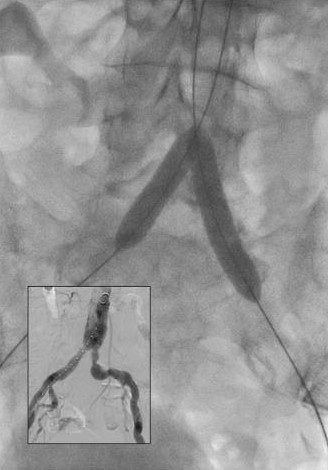

Widely patent arteries demonstrating VBX Stent Graft flexibility and radial strength in a highly tortuous vessel